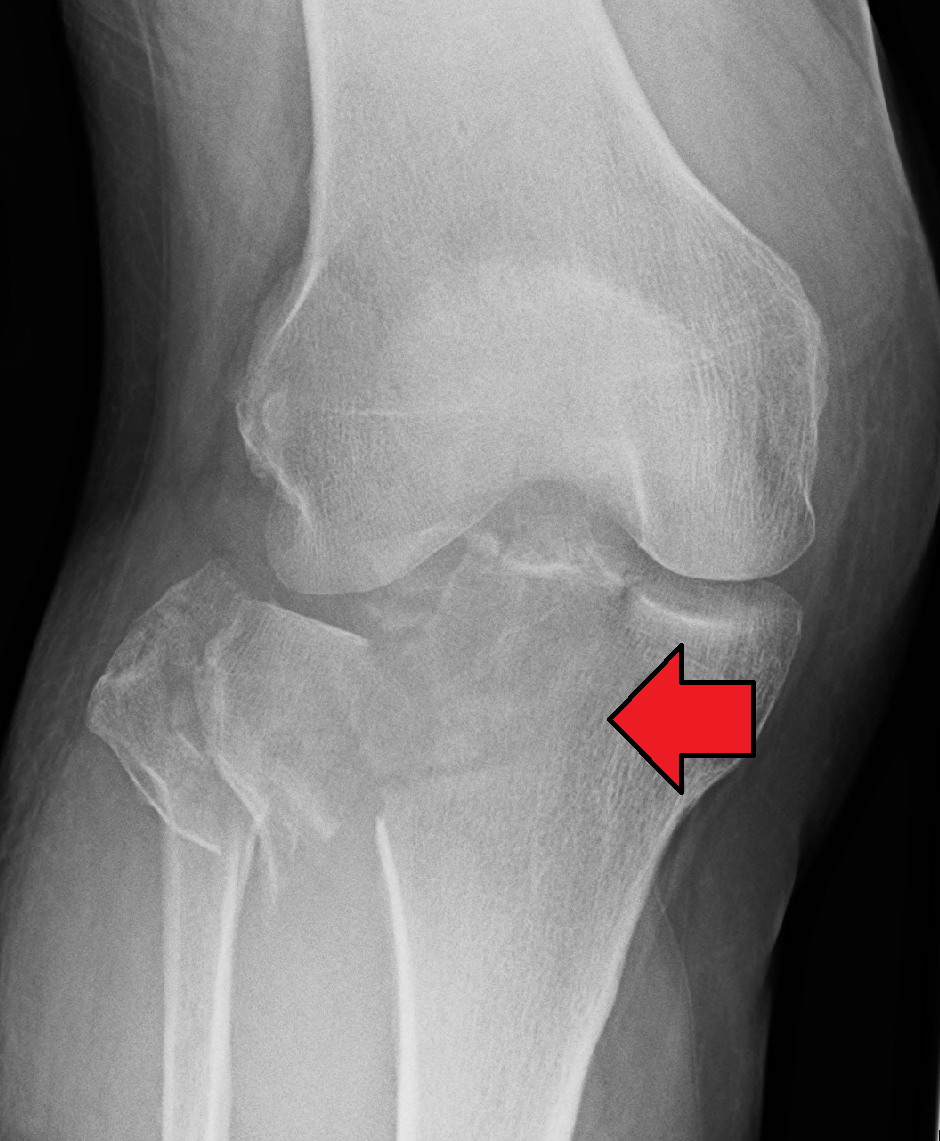

Транспозиция бугристости

Транспозиция бугристости 138 фото